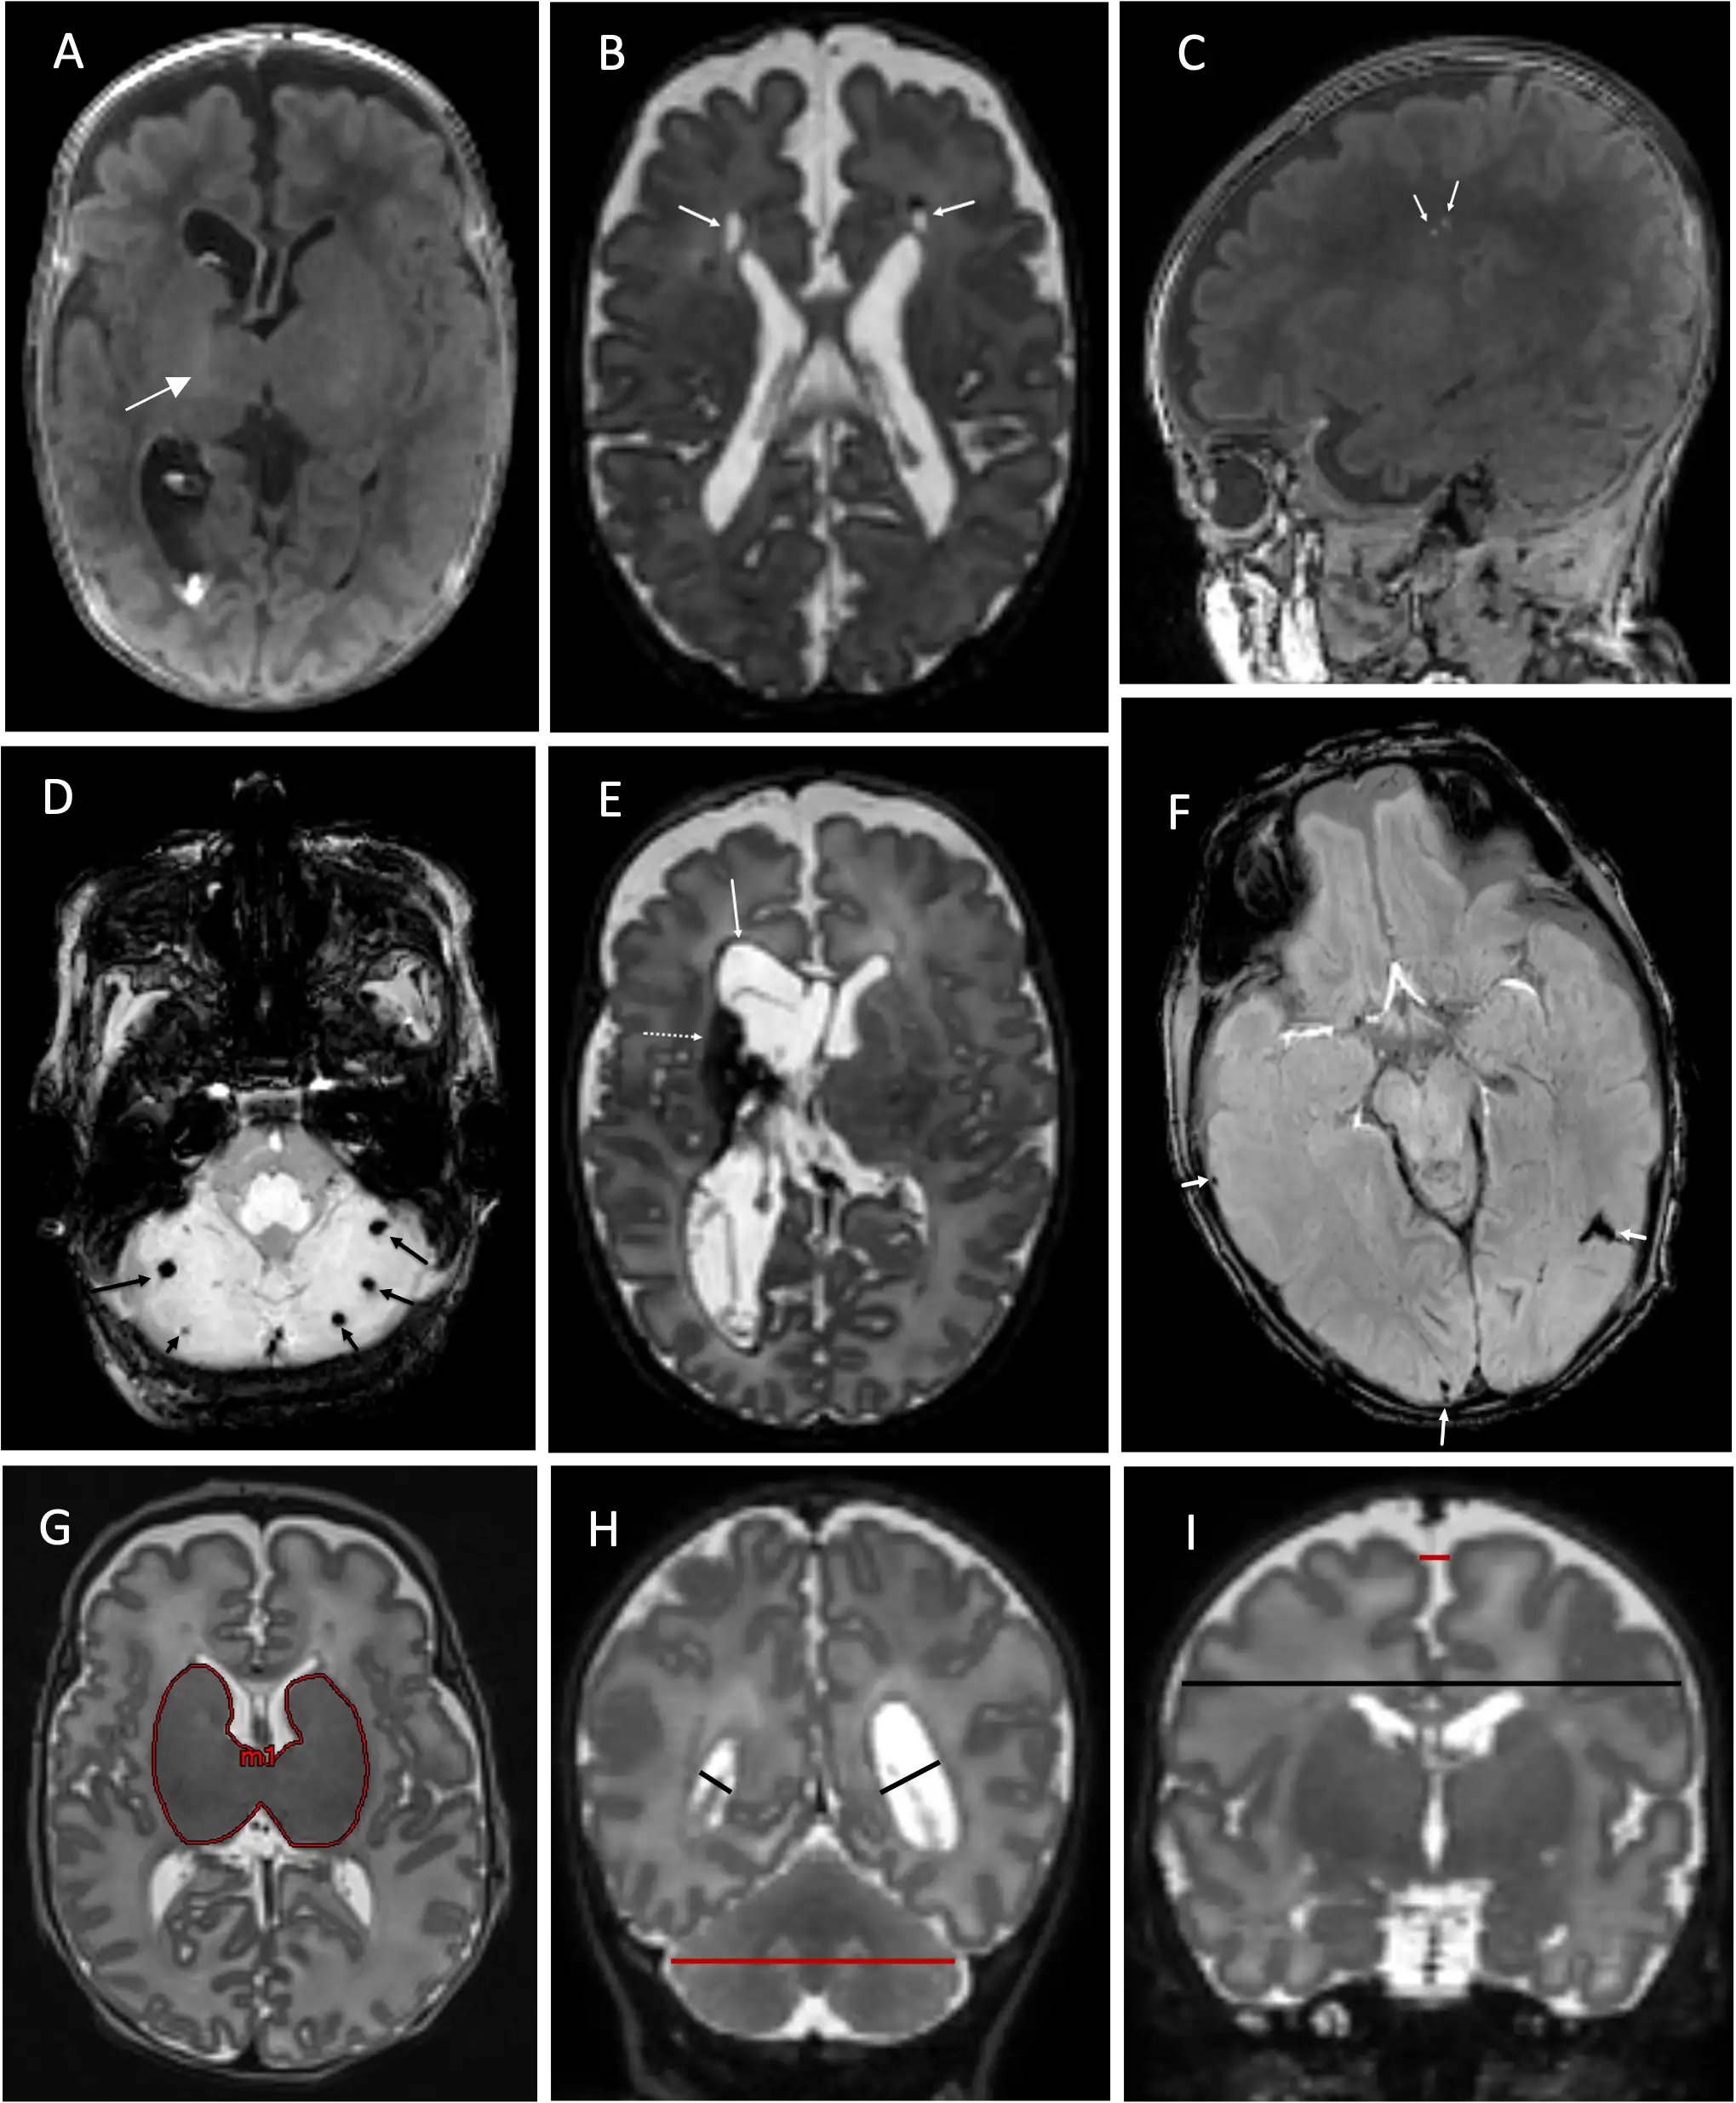

To test this, the CINEPS team examined MRI brain scans of 353 very preterm infants, 56 of whom had moderate to severe acute histological chorioamnionitis. They found that infants with at least moderate chorioamnionitis also had significantly higher brain abnormality scores than the control group.